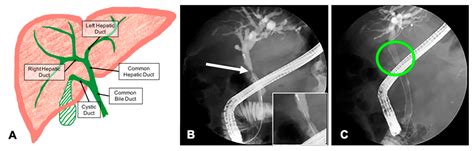

A bile duct stent is a synthetic tube—often made of plastic or metal—designed to be inserted into the bile duct to keep it open. The bile duct is a series of thin tubes that transport bile from the liver and gallbladder into the small intestine, where it aids in digestion. When this pathway becomes blocked, bile accumulates, leading to jaundice, severe pain, infection, or liver damage. The stent acts as a scaffold, ensuring that bile can flow freely into the digestive system once again.

These devices are primarily inserted via a procedure known as Endoscopic Retrograde Cholangiopancreatography (ERCP). During this minimally invasive procedure, a gastroenterologist uses an endoscope—a flexible, lighted tube with a camera—to navigate through the esophagus and stomach into the small intestine, reaching the opening of the bile duct to deploy the stent.

• Imaging: Using fluoroscopy (real-time X-ray), the doctor identifies the exact location of the blockage.

• Deployment: Once the location is identified, the stent is advanced through the endoscope and expanded within the narrowed area of the bile duct.

• bile duct stent removal procedure

• bile duct stent removal